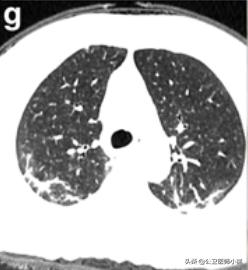

根据感染的不同程度累积一个或多个肺叶

肺部感染涉及多个肺叶-2